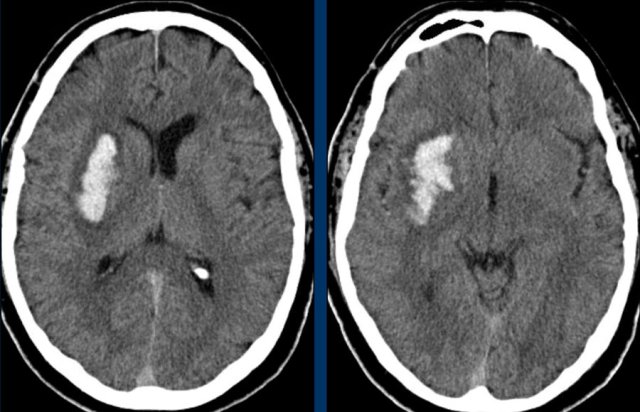

Right lower image is venous infarction due to sinus thrombosis (yellow arrows) Right lower image is venous infarction due to sinus thrombosis (yellow arrows)

Lobar hemorrhage

Lobar hemorrhages are located in the periphery of the cerebral lobes unlike hypertensive bleeding which usually is located more centrally.

The most common cause especially in elderly is cerebral amyloid angiopathy, but also hypertension because of its high prevalence.

Here some examples of lobar hemorrhages.

Bleeding into the ventricular system in lobar hemorrhage is not as common as in hypertensive hemorrhage because of the more periferal location.

Only when they are very large, they can cause bleeding into the ventricular system (fig).

This patient died the next day.

No definitive diagnosis was made, but it was assumed that this was a case of CAA.